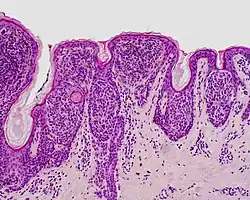

| Compound nevus | Both the epidermis and dermis.[17] |

ICD10: D22 (ILDS D22.L14) ICDO: 8760/0 | |

Characteristic rete ridge bridging, shouldering, and lamellar fibrosis. H&E stain. Characteristic rete ridge bridging, shouldering, and lamellar fibrosis. H&E stain.

|